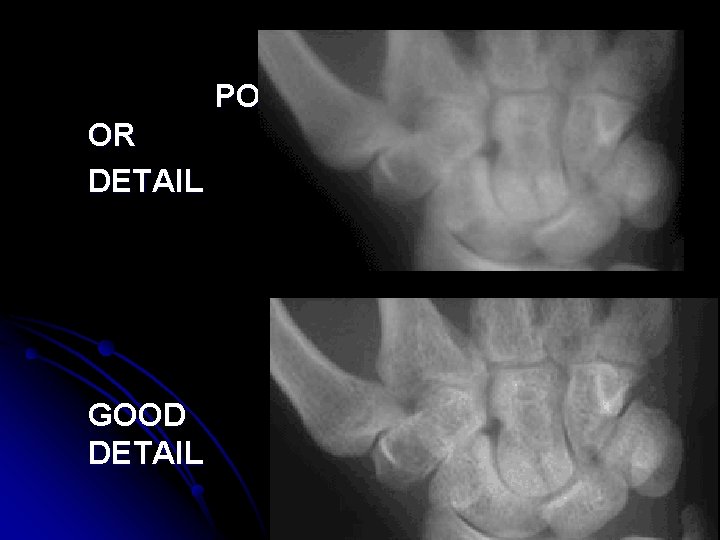

PO OR DETAIL GOOD DETAIL

DETAIL l. The degree of sharpness in an object’s borders and structural details. l. How “clear” the object looks on the radiograph

Recorded Detail l Other names: -sharpness of detail -definition -resolution -degree of noise